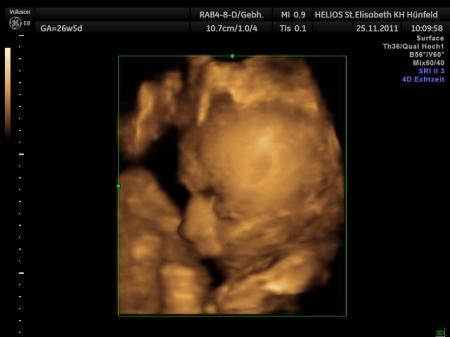

Meins ist auch noch nicht da - aber mein Wichtel und ich haben schon geschrieben und ich weiß das es noch kommt :D Euch schon Mal viel Spaß beim Auspacken am Sonntag - meld mich dann einfach wenn das Päckchen da ist - und vielleicht kommt es ja noch bis Samstag :D VLG. Änni, Oli und klein Eric im Bauchi

Bild zu